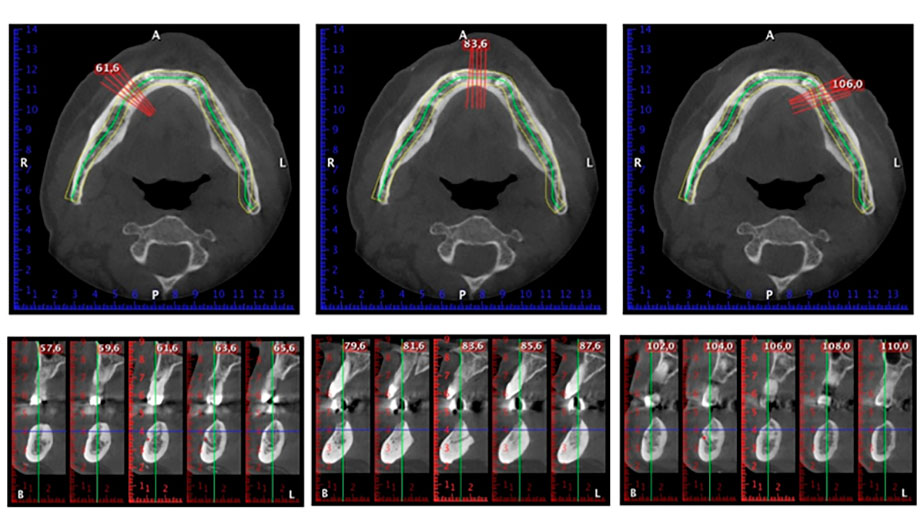

È stata eseguita una tomografia computerizzata Dentale Cone Beam in 3D (CBCT, con Planmeca) per aiutare la programmazione dell'intervento e la riduzione di rischi. L'esame ha evidenziato che la qualità e quantità dell'osso disponibile era sufficiente per eseguire l'intervento e la ricostruzione immediata, utilizzando il metodo Fast & Fixed. In base al protocollo del sistema, gli impianti sono stati inseriti in posizione 35, 32, 42 e 45. Gli impianti distali vengono installati a un angolo massimo di 45 gradi. Così facendo, il profilo che ne risulta viene spostato in posizione posteriore, generando un poligono di supporto più ampio (Fig. 3).

metodo Fast & Fixed

Fig. 3